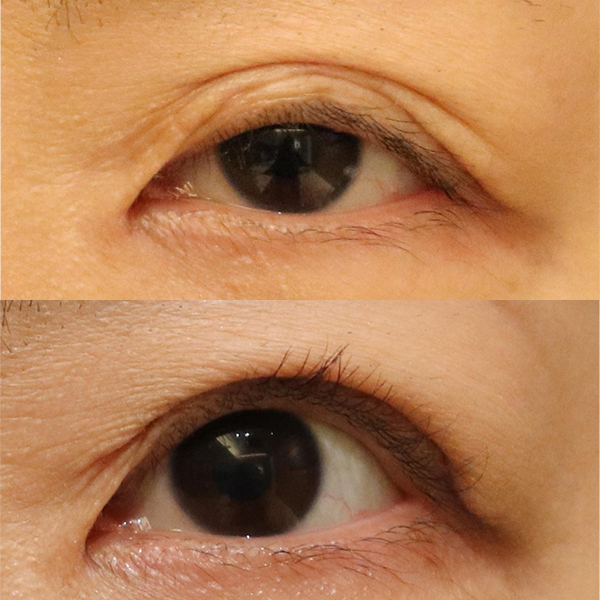

Since the shape of the eyelid became strange after the surgery, she underwent another revision surgery (skin excision) at the Plastic Surgery Department of Hospital C. However, the shape of the eyelid was still strange, so she came to our hospital hoping for a revision.

As one would guess, the patient had surgery performed by her previous surgeon.

I would guess that the heavy eyelids were created exactly as they were in the previous surgery, but the heavy eyelids were created too high. We often see patients in a similar condition after cosmetic or plastic surgery for droopy eyelids.

The position of the eyelid is not necessarily higher than the eyelid should be. If the eyelids are not in the proper position, the skin under the eyelids will sag, resulting in this condition.

The size of the black eye has increased, but the skin laxity has increased relative to the size of the eye, and the position of the eyelid is unnatural. Our surgery included additional skin excision, including the improperly positioned eyelid, and creation of a properly positioned eyelid.

The patient's eyes were open before surgery, but you can see the improvement after surgery.

| Before surgery | Although there is a double eyelid, it is positioned too high and the skin underneath is sagging, so the eyelid cannot be opened properly. |

|---|---|

| After surgery | The double eyelid position was lowered to 5 mm above the eyelashes and additional skin was excised to create a double eyelid. The preoperative unnatural skin laxity was corrected. |

| Before surgery | The skin under the double eyelid is sagging and cannot be opened tightly. This causes the eyes to appear as if they are wide open. |

|---|---|

| After surgery | A double eyelid was created lower than the original and additional skin was removed. The preoperative unnatural skin laxity has disappeared, and the open look of the eyes has improved. |